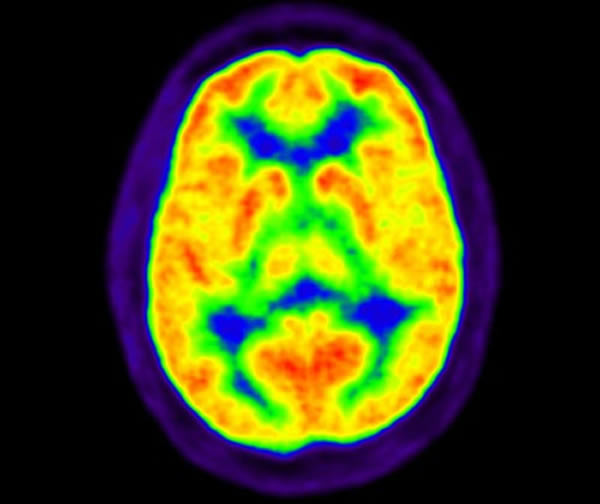

据了解,该研究小组是由亚历山大-希尔瓦和乔恩—卡尔—祖比尔塔博士负责的,他们在实验中使用了一个名为“经颅直流电模拟器”(tDCS)的装置,并让一位患有重度慢性面痛的病人参与该实验,他们用应用电极中非常小的电流来刺激头盖骨的某个特定区域达20分钟之久,研究人员发现该电流使大脑释放出“天然止痛药”,也就是所谓的内源性阿片类物质,最为特别的是,该物质改善了这名患者痛阈的36%。科学家在这个实验阶段,用正电子发射层析扫描监视了整个试验过程。尽管这种物质不能完全祛除临床疼痛,但科学家表示,如果反复持续进行电流的刺激,就可以具有很好的疗效。